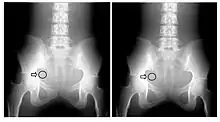

A second parameter to be derived from the transfer characteristic is the dynamic range, which expresses the range of input signals over which the image receptor is sensitive. In the case of CR, its about four orders of magnitude - see Figure 6.3, which shows its transfer characteristic in comparison to the traditional film/screen technology. The result is that under-exposure and over-exposure of regions traditionally seen radiographs are much less of an issue in clinical imaging. This feature of CR is illustrated by the radiographs in Figure 6.4.

The maximum spatial resolution of an imaging system can be readily obtained by imaging a resolution test object - an example of which is shown in Figure 6.5, panel (a). The test object consists of narrow parallel slits in a lead sheet at spacings which decrease to beyond the maximum resolution of the image receptor. The minimum spacing resolved in images is called the Limiting Spatial Resolution and can be determined to be about 3.5 line pairs/mm from the figure.